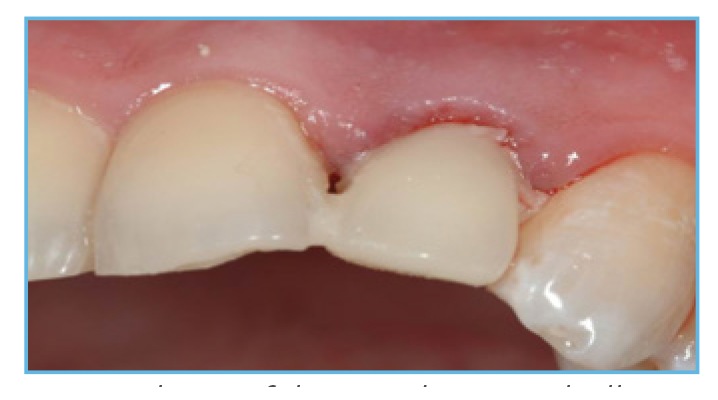

Fig. 3. The PreFormance Post was prepared intraorally to follow the gingival contours.

Fig. 4. The prefabricated crown shell was luted to the PreFormance Post.

Fig. 5. The provisional restoration was fabricated, occlusal and interproximal contacts were checked, adjusted accordingly, and delivered to the patient.